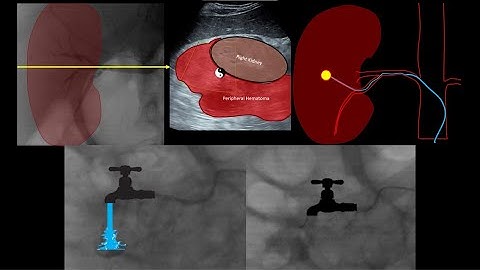

Embolisation of renal artery pseudoaneurysm post partial nephrectomy